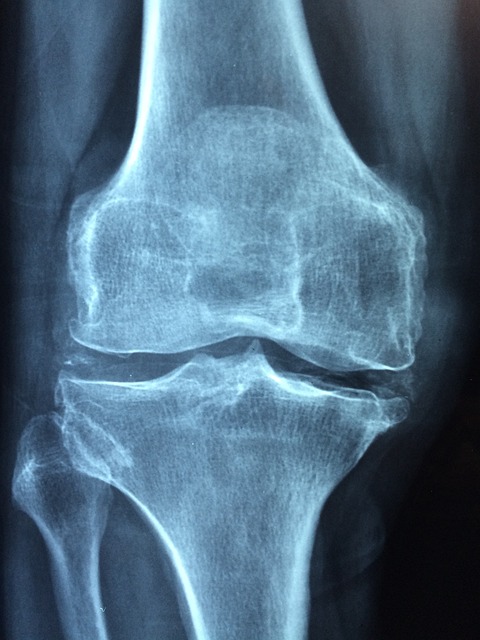

1. 골밀도 유지 및 골다공증 예방

MBP를 일정 기간 섭취하면 골밀도가 유지되거나 향상되는 결과가 관찰됩니다. 폐경기 여성이나 50대 이후 남성에게 특히 유용합니다.